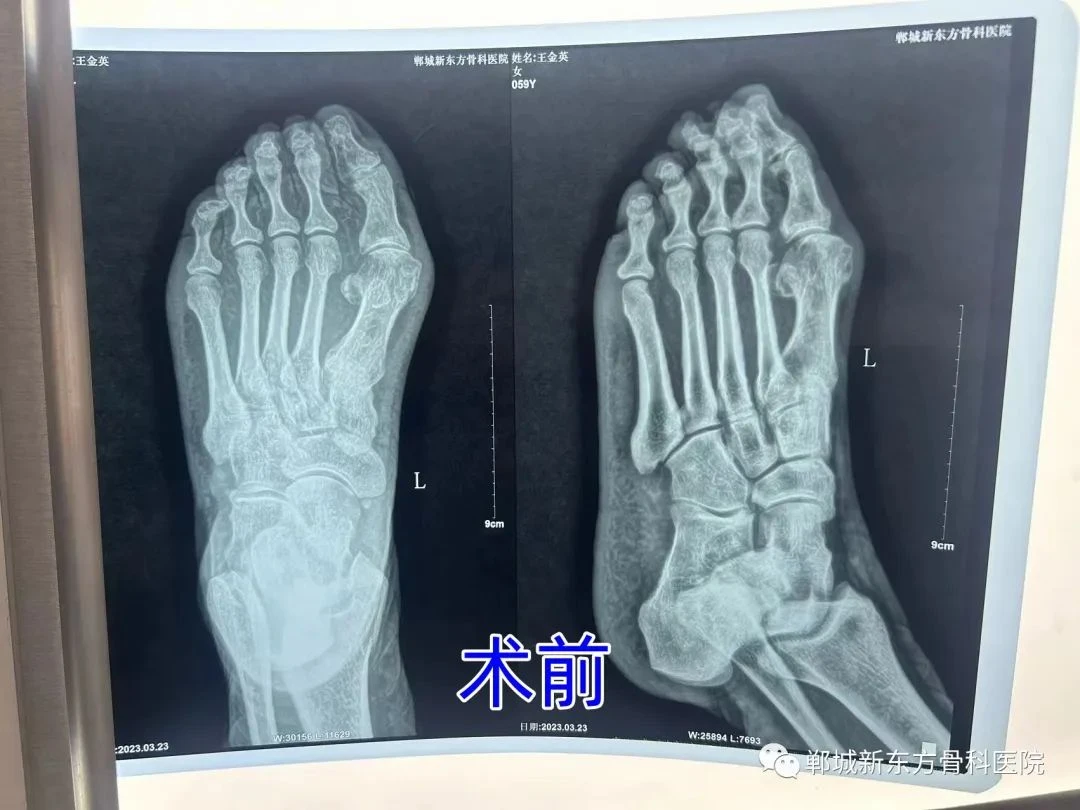

郸城新东方骨科医院特殊病例

我县王女士,59岁,自诉5年前无明显诱因,走路出现疼痛,活动或者穿鞋都非常不便,门诊以“左拇外翻”收住入院。于3月23日行 趾闭关节融合术,手术非常成功,术后患者便可下床活动。经两个月随访,患者现在已恢复正常。